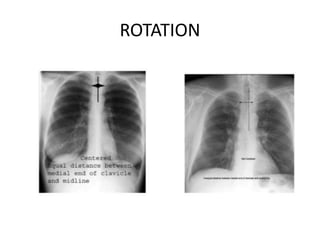

This document provides an overview of interpreting chest x-rays and identifies several key factors. It discusses the importance of inspiration, penetration, and rotation in obtaining a technically quality radiograph. It also outlines different views of chest x-rays including PA, AP, and lateral views. Finally, it identifies several anatomical structures that should be evaluated when interpreting a chest x-ray such as the lungs, heart, diaphragm, bones, and soft tissues.